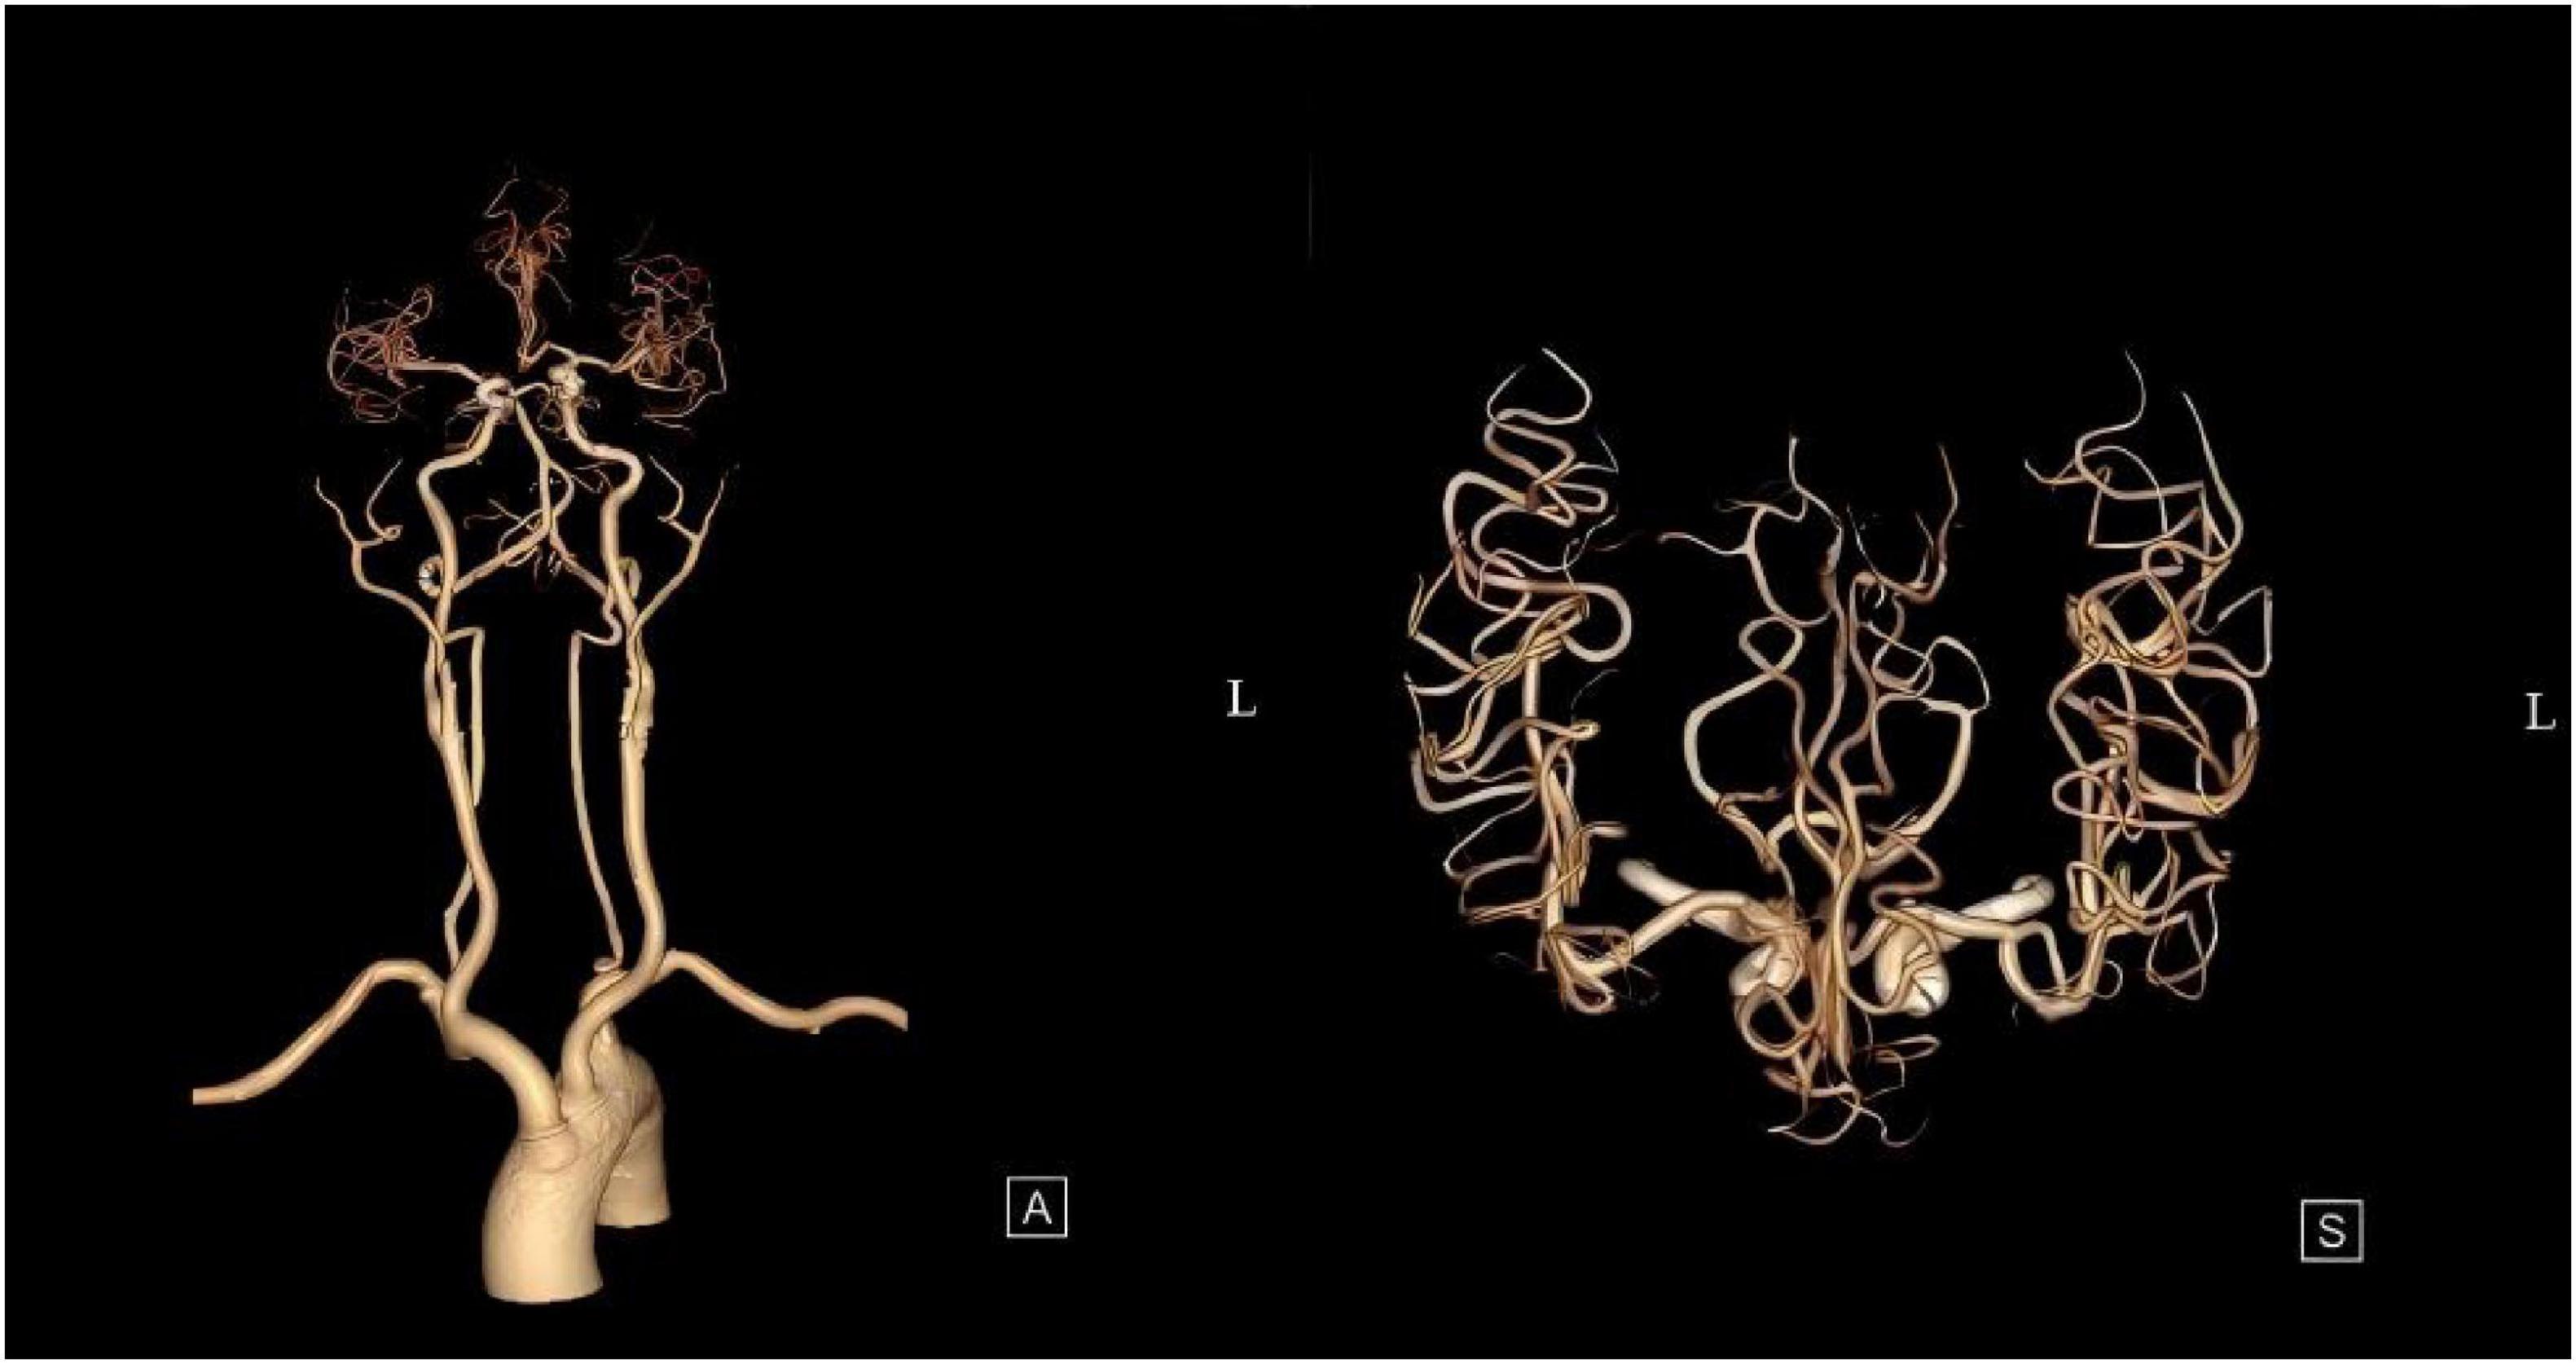

The patient was admitted to the hospital, and a cranial vascular CTA examination revealed cerebral atherosclerosis without obvious vessel stenosis (see Figure 1); a cranial MRI and DWI examination revealed bilateral cerebellar, bilateral frontal-parietal-temporo-occipital, and semiovoid central region infarcts (see Figure 2A); troponin levels were 0.224 ng/ml [ref (ref), 0.0–0.08 ng/ml], Creatine kinase isoenzyme 34 U/L [ref, 0.0–24 U/L], N-terminal brain natriuretic peptide precursor (BNP) 1324 pg/ml [ref, 0.0–300 pg/ml], and an electrocardiogram that suggested an ST-segment abnormality. Cardiovascular consultation was sought to rule out a non-ST-segment elevation myocardial infarction, and antiplatelet aggregation and lipid-modulating therapy were administered. The percentage of eosinophils was 43.4% [ref, 0.4%–8%], and tests for coagulation function, lipids, and liver and renal function revealed no appreciable abnormalities. Two days later, the patient developed severe precordial discomfort and dyspnea. Concurrently, limb muscle strength decreased significantly. On March 31, a physical examination revealed grade 3 muscle strength in the left upper limb, 0 in the right upper limb, and grade 2 muscle strength in both bottom limbs. Figure 3 depicts muscle strength scores provided by the Medical Research Council (MRC). Troponin, creatine kinase isoenzyme, and eosinophil percentage were all steadily declining compared to the prior time frame. As shown in Figure 3, the acidophilic fraction increased steadily. He was moved to the critical care unit (ICU) on March 31 in order to receive correctional treatment. According to a perfect coronary CTA examination, the coronary artery wall had many segmental mixed plaque formation, mild stenosis in the lumen, and an anterior descending branch of the middle section of the stent, which was about 2.3 cm long. The stent did not exhibit any visible fractures or restenosis symptoms, as shown in Figure 4. Bilateral cerebellum, bilateral frontal-parietal-temporo-occipital and semiovarian central area of several spots, and a tiny patchy DWI high signal, measuring between 2 and 18 mm (slightly larger in extent than the previous MR 2025.03.27), were all suggested by the review of the cranial MRI test (see Figure 2B). On April 1, tests revealed a considerably higher eosinophil level. Eosinophilia was discovered following a consultation with the hematology department. To decrease eosinophils, methylprednisolone sodium succinate was administered first, followed by clopidogrel to limit platelet aggregation and low molecular weight heparin for anticoagulation. A bone marrow aspiration was performed to assess flow cytometry, FISH, and fusion genes. Figure 5A shows the flow cytometry results for April 5: an elevated eosinophil percentage. According to the bone marrow aspiration report, there were more eosinophils in the bone marrow and peripheral blood images. Figure 5B shows an increase in eosinophils. Fusion gene screening revealed no results for PCM1:JAK2, ETV6:JAK2, FLT3, ETV6:ABL1, and BCR:JAK2. FISH probe analysis: FGFR1, PDGFRA, and PDGFRB: negative. Low molecular heparin anticoagulation, clopidogrel antiplatelet aggregation, and eosinophils were all reduced by methylprednisolone sodium succinate. Eosinophil counts in the patient progressively returned to normal. The patient’s limb muscle strength improved between 4 and 11; both upper and lower limb muscular strength were grade 3 and grade 4, respectively. He was sent to the rehabilitation department for therapy, and on April 28, he was released from the hospital on June 1. The outpatient follow-up assessment showed that the patient’s limb muscle strength had restored to normal.

FIGURE 1

Cranial vascular CTA suggestive of cerebral atherosclerosis.